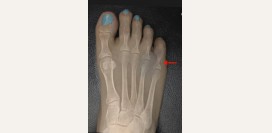

Болят пальцы ног. Болят косточки пальцев ног. Причины болей в пальцах ног. Боли при ходьбе. Патологии, вызывающие болезненность. Помощь при болях в пальцах ног

127059

0